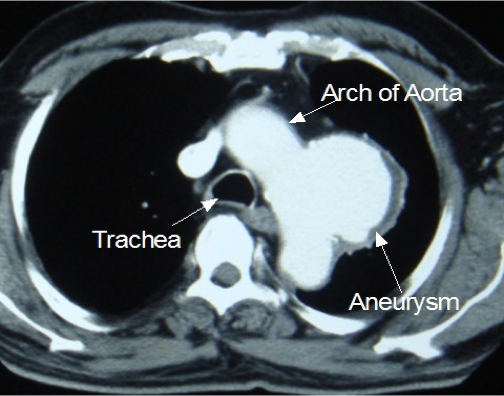

What does this CT refer to

Thoracic Aneurysm